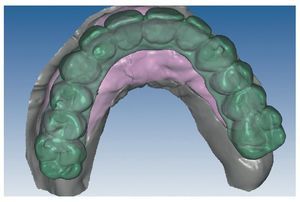

Mediante el uso de un escáner óptico de luz estructurada, los protocolos CAD registran los primeros datos relativos al modelo maestro con las correspondientes posiciones de implante (figs. 87 y 92). En el siguiente paso tiene lugar la digitalización de la planificación, previamente realizada en cera de escaneo matificada, de la restauración definitiva (figs. 88, 90 y 93). La subsiguiente conciliación de los datos mediante el uso del software de diseño dental permite al protésico planificar virtualmente el resto del procedimiento (figs. 89 y 91, 94 a 96) a partir del diseño de las estructuras (figs. 97 y 98).

Fig. 88. Imagen CAD de la planificación definitiva para el maxilar superior.

Fig. 89. Planificación CAD de la estructura del maxilar superior.

Fig. 91. El diseño definitivo de la estructura para el maxilar superior.

Fig. 93. Imagen CAD de la planificación definitiva para el maxilar inferior.

Figs. 94 a 95. Planificación CAD de la estructura del maxilar inferior, en representación lingual y vestibular.

Figs. 96 a 98. El diseño definitivo de la estructura del maxilar inferior, desde distintas perspectivas.